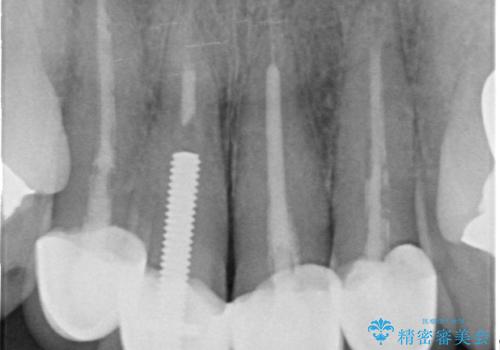

- 20年前に治療した前歯の劣化・審美障害の改善を求めて来院されました。

クラウンを除去し審美的なジルコニアクラウンによる補綴の再作製計画を立案します。

- 52万円(仮歯×4・ファイバーコア×4・ジルコニアクラウン×4)費用は治療当時の料金となります

クラウンと支台の適合が悪いと内部に汚れがたまり虫歯の再発・審美性の障害・口臭の発生リスク方あまります。